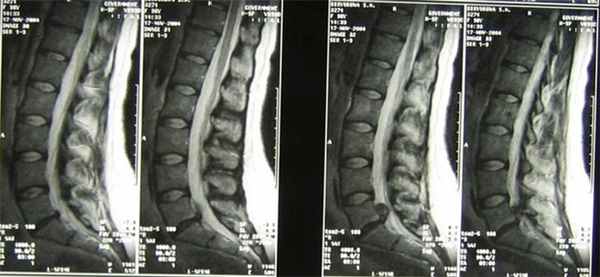

При проведении МРТ, кроме стандартных исследований в Т1-и Т2-режимах, для улучшения визуализации установленной биодегра-дируемой мембраны получаемые Т2- взвешенные изображения (Ш500, ТЕ 118) дополняли изображениями, взвешенными по протонной плотности с подавлением МР-сигнала от жировой ткани. Режим сканирования основан на импульсной по-

следовательности «инверсия - восстановление» при TR1940, ТЕ 31,3. Выбираемые значения FOV 20/20 толщины среза 4 мм при шаге сканирования в 1 мм были при первом и втором режимах сканирования одинаковы. Дополнение традиционных Т2 ВИ-изображениями в режиме PDFS позволило получить дополнительную информацию о соотношении мембраны с окружающими анатомическими структурами за счет снижения интенсивности МР-сигнала от жировой клетчатки, что позволяет более четко определять положение мембраны (рис. 1).

Средний срок катамнеза составил 1,8 года (от 6 мес. до 4 лет). В послеоперационном периоде оценку качества жизни проводили по опроснику Освестри, болевого синдрома -по ВАШ. Дополнительно оценивали клинические проявления радикулопа-тии, а также МРТ пояснично-крестцо-вого отдела позвоночника на доопе-рационном этапе и после операции в динамике (рис. 2).

При проведении МРТ через 10 дней Т2-взвешенные изображения в режиме PDFS позволили получить дополнительную информацию о соотношении мембраны с окружающими анатомическими структурами за счет снижения интенсивности МР-сигнала от жировой клетчатки, что позволяет более четко определять положение мембраны. Sj корешок изолирован мембраной от прилежащих структур: передних, включающих заднюю продольную связку, входные ворота грыжевой компрессии, задней поверхности тел позвонков; боковых, включающих фасеточные суставы и ножки; задних, включающих мышечно-свя-зочный аппарат. Спустя 6 мес. после микродискэктомии визуализируются послеоперационные изменения прилежащих структур, отграничение сосудисто-нервного пучка от окружа-

МРТ (PDFS-режим, аксиальный срез) в динамике через 3 мес.: на фоне послеоперационных изменений визуализируется мембрана (стрелка), изолирующая нервный корешок и твердую мозговую оболочку от окружающих структур

ющих структур и рубцово-изменен-ных тканей.